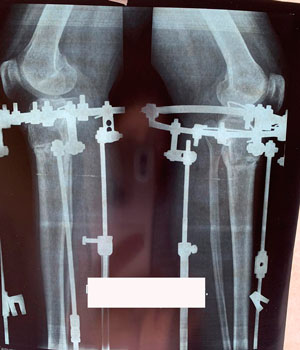

Дата операции - 17.10.2019г

Дата снятия аппаратов - 14.02.2020

Срок сращения - 117 дней.